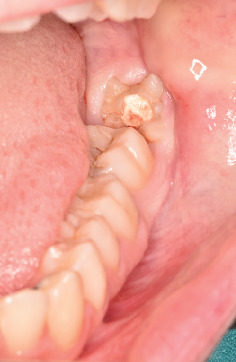

Introduction: Gemination and fusion are rare developmental anomalies that can present significant diagnostic challenges. Due to the complexity of distinguishing between these conditions, the term "double tooth" is commonly employed in clinical practice. The precise etiology of these anomalies remains uncertain, and their occurrence in permanent dentition-particularly involving molars-is exceptionally rare. This report describes an uncommon case of gemination affecting the mandibular left third molar (tooth 3.8) and provides a comprehensive discussion contextualized within existing literature. The case report was prepared following the CARE guidelines to ensure methodological rigor and completeness. Methods: After an intraoral examination and radiographic assessment-including orthopantomography, periapical radiographs, and cone beam computed tomography (CBCT)-the patient underwent surgical extraction. The procedure involved administering a truncal nerve block to anesthetize the inferior alveolar and lingual nerves, supplemented by local infiltration anesthesia of the buccal nerve. A full-thickness mucoperiosteal flap was elevated, followed by ostectomy and odontotomy to facilitate extraction. The tooth was subsequently removed using a combination of elevators and forceps. Results: Postoperative evaluations conducted at 1.5 and 3 months confirmed complete healing of the surgical site. A detailed analysis of pre- and postoperative radiographic and clinical findings validated the diagnosis of gemination, characterized by coronal continuity with a single root and root canal. Conclusions: Gemination of third molars is exceedingly rare, with only a few cases documented in the literature. To the best of our knowledge, this is the first reported instance of gemination involving the mandibular left third molar (tooth 3.8). This report contributes to the growing body of knowledge on developmental dental anomalies and highlights the importance of thorough differential diagnosis in similar clinical scenarios.

Abstract Image